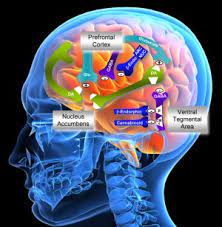

قیمت: 96٬000 تومان - دسته بندی فایل: پاورپوینتپاورپوینت فیزیولوژی اعصاب

فروش ویژه پاورپوینت حرفه ای فیزیولوژی اعصاب / تعداد اسلاید: 231 اسلاید

قیمت: 59٬000 تومان - دسته بندی فایل: پاورپوینتپاورپوینت فعالیت نیم کره ی مغز و برتری اندام ها

فروش ویژه پاورپوینت حرفه ای فعالیت نیم کره ی مغز و برتری اندام ها / تعداد اسلاید: 55 اسلاید